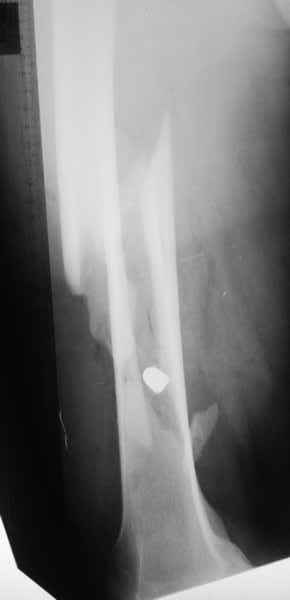

Пуля от ПМ - очевидно, что ранение было т.н. низкоэнегетическим, что подтверждается в том числе спокойным состоянием мягких тканей в этом, уже отсроченном периоде.

Однозначно, огнестрельные переломы стоит стабилизировать АНФ в максимально ранние сроки после получения ранения. Так же при ПХО или повторной ХО требуется фасциотомия. Эти две манипуляции приводят к улучшению паравульнарного кровотока и уменьшают вероятность развития вторичных осложнений. Дождавшись закрытия ран и при полной уверенности в отсутствии гнойных осложнений можно поднимать вопрос о конверсии наружного остеосинтеза на внутренний. Судя по снимку, пуля пистолетная, перелом не носит многооскольчатый характер, что дает основание полагать, что невысокая энергия ранения подразумевает невысокую вероятность вторичных осложнений и возможность внутреннего остеосинтеза. Конечно, БИОС в а\б муфте предпочтительнее ввиду щадящего отношения к кровообращению в заинтересованной области, но лучшая методика та, которой хорошо владеет хирург.

Небольшие входные пулевые раны до 1 см (см. на снимке) закрываются в течение нескольких дней самостоятельно даже без обработки. Раны более 3 см также не нуждаются в специальной обработке, и для самостоятельного закрытия ран бывает достаточной обычная обработка стенок раны "кюретажем".

Характерным признаком травмы с низкой кинетической энергией является отсутствие "мультифрагментации и кавитации", и поэтому в данном случае лечение можно проводить любым доступным методом.